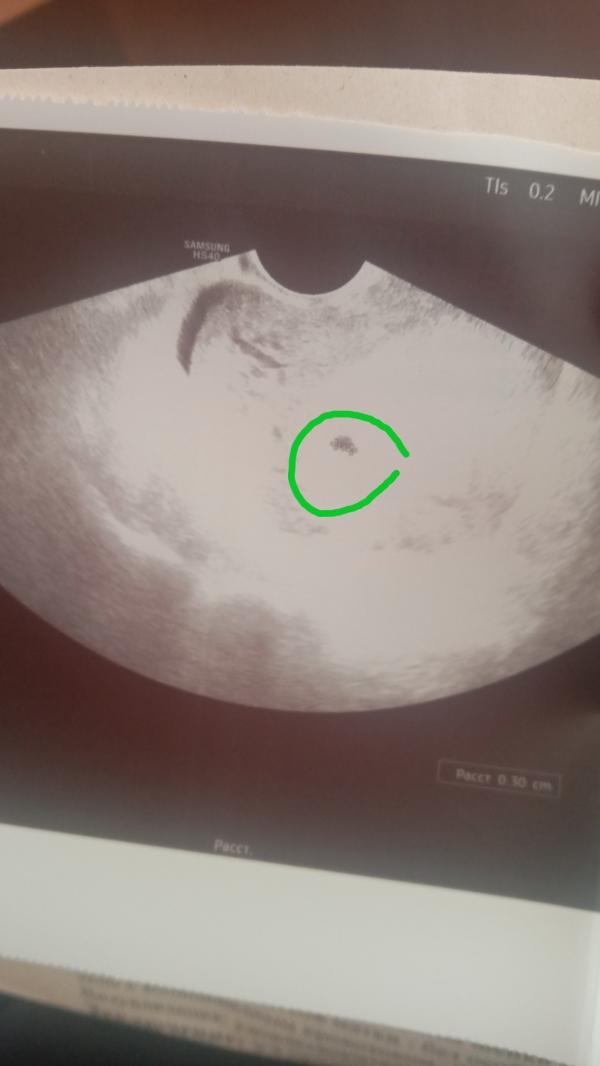

Здравствуйте девочки ну я все же не могу понять как ведеться расчет вся запуталась первый день последних месячный был 31.05.2022.ждали 2 полоски первое узи сделали 5.07.2022 поставили беременность 3 недели. Яйцо плодное 3 мм желточного мешечка небыло .Второе узи я сделала 13.07.2022 прошла неделя ставят 5 недель плодное яйцо 18мм желточный мешечек 2 мм эмбриончика еще нет. За неделю выросло в 6 раз . вот и не пойму как считают и какой у меня срок и все ли по сроку норма

@viktoriaazykova1 я Вам уже сказала, что считают они некорректно. Нет такого акушерского срока 3 недели, его на узи не видно. Второй протокол, где 5 недель акушерских написано, скорее всего, по размерам плодного яица посчитано. Но по факту у Вас уже 7 должно быть, а не 5.

По акушерскому сроку у Вас 8 недель и 2 дня, эмбрион уже должен быть и сердцебиение. Плодное яйцо растет, но пустое. Здесь два варианта, либо поздняя овуляция либо анэмбриония. УЗИ ставит тоже акушерский срок, не от зачатия. Если есть сильные разногласия, больше 2-х недель, то не исключено, что есть проблемы в развитии беременности.